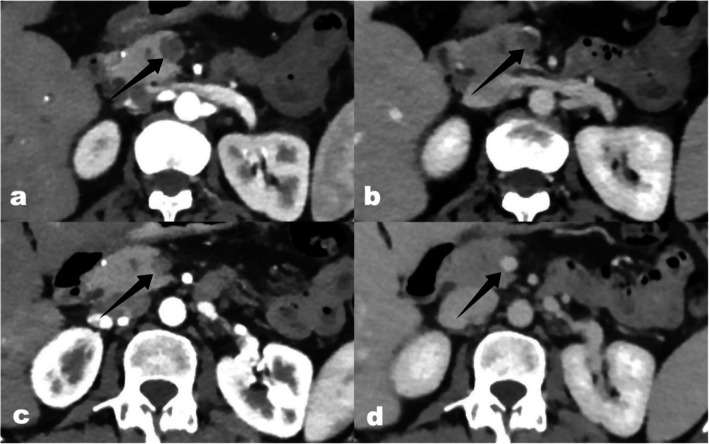

Methods: Between August 2019 and May 2024, 12 patients (males = 9; mean age, 52.33 ± 12.51 years) were diagnosed with ASMVT. The study collected comprehensive data on demographic details, presenting symptoms, etiology, treatment modalities, response to treatment, and follow-up outcomes. Computed Tomography (CT) was available from diagnosis, and an average of 6.3 CT scans with a median follow-up of 3 months (IQR: 2-20 months).

Results: The average time from symptom onset to angiographic treatment initiation was 8.0 ± 4.71 days, preceded by anticoagulation with heparin from the time of diagnosis. Patients were treated with combination therapy involving endovascular thrombolysis, rheolytic thrombectomy, and balloon angioplasty via transjugular (n = 9, 75%) or percutaneous (n = 3, 25%) approaches. Thrombolysis was performed with an average recombinant tissue plasminogen activator (rt-PA) infusion duration of 2.75 ± 1.14 days and a total dose of 61.25 ± 18.48 mg rt-PA. Superior mesenteric vein (SMV) flow was initially restored almost completely in 58.3% and partially in 41.7% of patients. Complications observed were hepatic artery bleeding (n = 2, 16.7%), hepatic arteriovenous fistula (n = 1, 8.3%), hepatic parenchymal bleeding (n = 1, 8.3%), melena (n = 1, 8.3%), and nostril bleeding (n = 1, 8.3%). Two patients experienced worsening symptoms of post-intervention, leading to bowel resection revealing intestinal necrosis. SMV patency was almost complete in 25%, and partially in 25% of patients at follow-up.